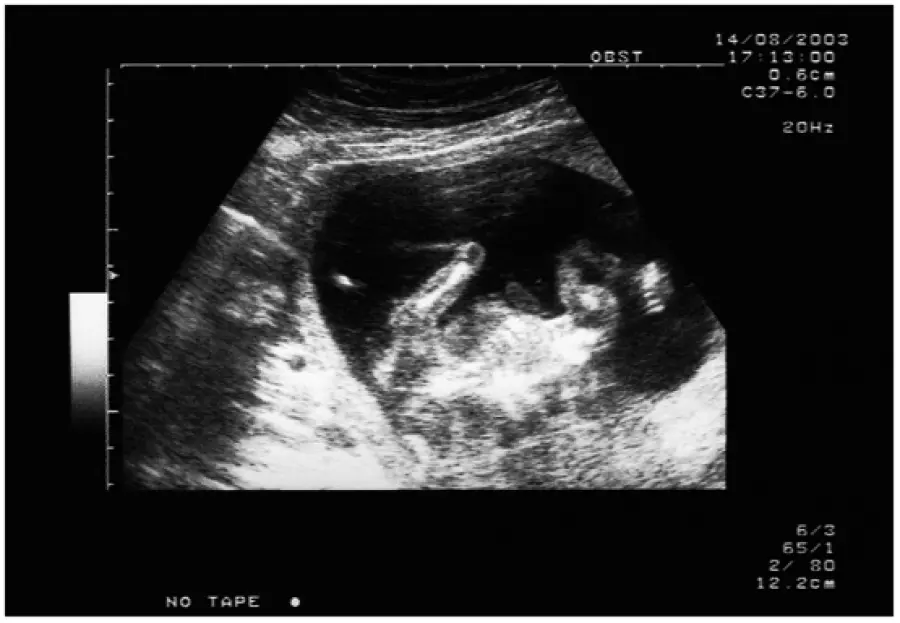

Esistono comunque anche tecniche di tipo non invasive, prima fra tutte l’ecografia, il cui sviluppo, ha permesso di mettere a punto esami di screening ad alta sensibilità, quali il testcombinato (bitest + translucenza nucale) e lo sca test, ambedue basati sulla misurazione ecografica di parametri anatomici e funzionali del feto e sul risultato di esami ematochimici, che forniscono valori statistici molto accurati, che all’occorrenza, possono indirizzare verso esami diagnostici.

Fra tali tecniche, rientra anche l’ecografia morfologica, del secondo trimestre di gravidanza, che può evidenziare eventuali malformazioni o anormalità fetali e l’ecocardiografia fetale che analizza sempre ecograficamente, il cuore del feto sia anatomicamente, che sotto il profilo dinamico-funzionale; tale tecnica, non rivela però malattie genetiche.